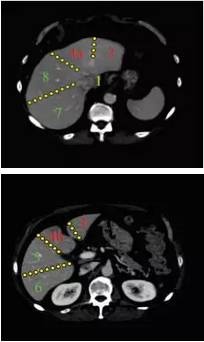

简单记忆方法:

上:7 8 4 2

下:6 5 4 3

http://webres.medlive.cn/upload/000/516/239